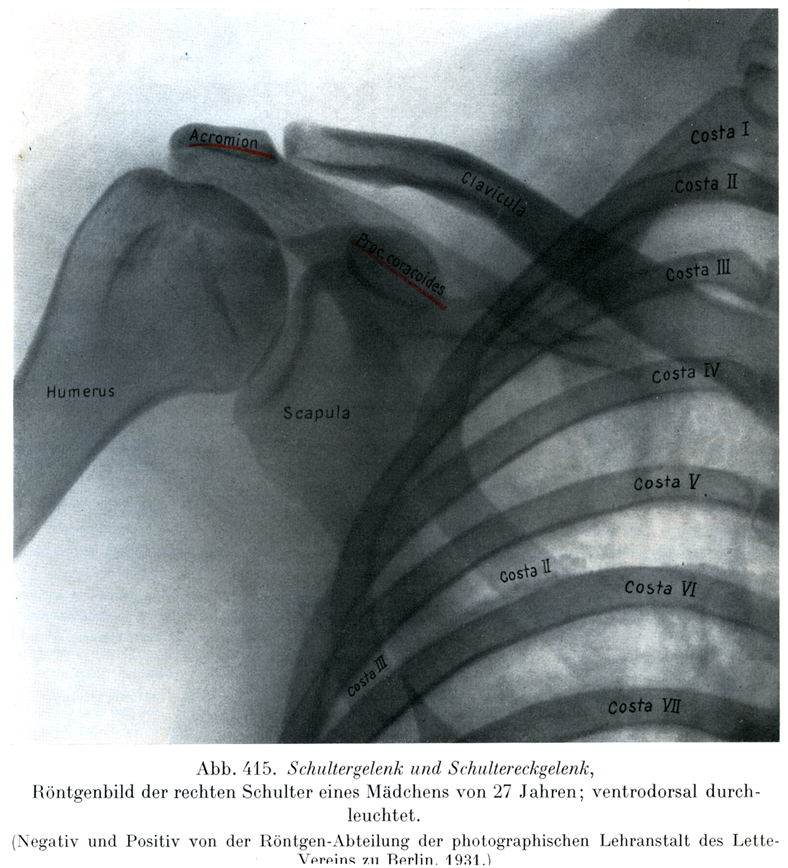

[図415] 肩関節と肩鎖関節 27才の処女の右肩のレントゲン像,腹背照射.